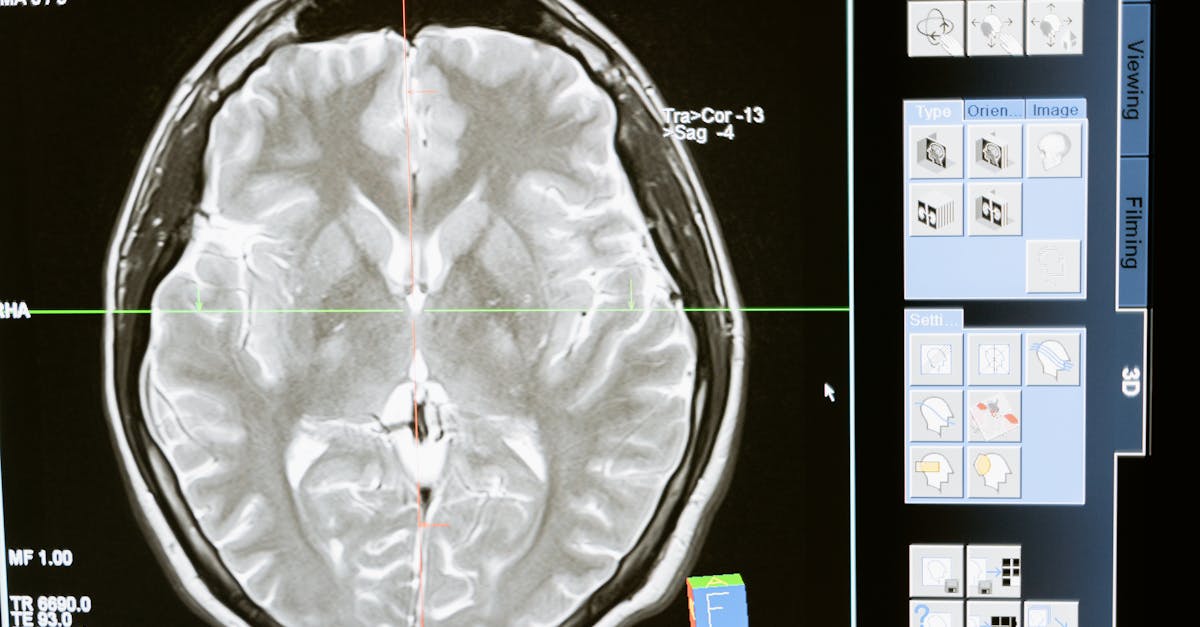

Après l’évaluation initiale, des examens d’imagerie sont nécessaires pour confirmer le diagnostic. Les radiographies et l’IRM (Imagerie par Résonance Magnétique) sont des outils précieux. Ces examens permettent de visualiser l’état de la colonne vertébrale et d’identifier les zones de compression des nerfs. Ils sont indispensables pour comprendre la gravité de la sténose et son impact sur le patient.

Pour confirmer le diagnostic, des examens d’imagerie médicale tels que les radiographies, l’IRM (Imagerie par Résonance Magnétique) ou les CT scans (scanners) sont souvent nécessaires. Ces examens permettent de visualiser la colonne vertébrale, les disques intervertébraux ainsi que les structures environnantes, identifiant ainsi les potentialités de compression nerveuse.

L’IRM est particulièrement recommandée car elle offre une meilleure visualisation des tissus mous, révélant des hernies discales ou des rétrécissements dans le canal vertébral, qui sont indicatifs de sténose spinale.

| Imagerie médicale | Réaliser des radiographies ou une IRM pour visualiser les structures de la colonne vertébrale. |

Une fois l’examen physique réalisé, il est souvent nécessaire de recourir à des examens d’imagerie médicale. Les radiographies peuvent être exécutées en premier lieu pour visualiser la structure des os de la colonne vertébrale. Cependant, une IRM (Imagerie par Résonance Magnétique) est généralement recommandée pour obtenir une image plus claire des tissus mous, y compris des disques intervertébraux. L’IRM permet de détecter la présence de hernies discales, d’élargissement des ligaments et d’autres anomalies pouvant entraîner une sténose.

Les examens d’imagerie médicale, tels que les radiographies et les IRM, sont inévitables dans ce parcours diagnostique. Ils fournissent des visualisations précieuses de la colonne vertébrale, permettant de confirmer la présence d’une sténose ainsi que d’éventuels pincements discaux. Ces outils sont essentiels pour évaluer l’impact de la sténose sur les structures nerveuses et déterminer le degré de compression.